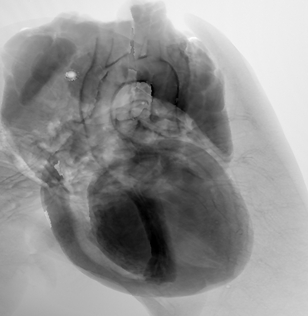

マウス心臓

結晶干渉法

17.8 keV

30秒

(投影像)

試料提供:北里大学Lwin准教授